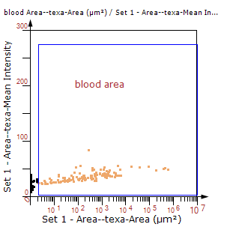

5. 识别血管的Texa Red染色区域面积及强度。

血管识别:根据Texa Red通道进行识别,并去除面积小的及非同一焦面的血管,仅对确定的清晰的同一焦面的大血管进行面积统计。

根据染色强度,染色面积,细胞形态学,利用正反向回溯功能和设门圈选Gating,排除杂质,细胞碎片,黏连细胞(绿色框线标记),获得有效的神经元胞体,(粉色框线标记),并将胞体按照面积分为两类(散点图)。